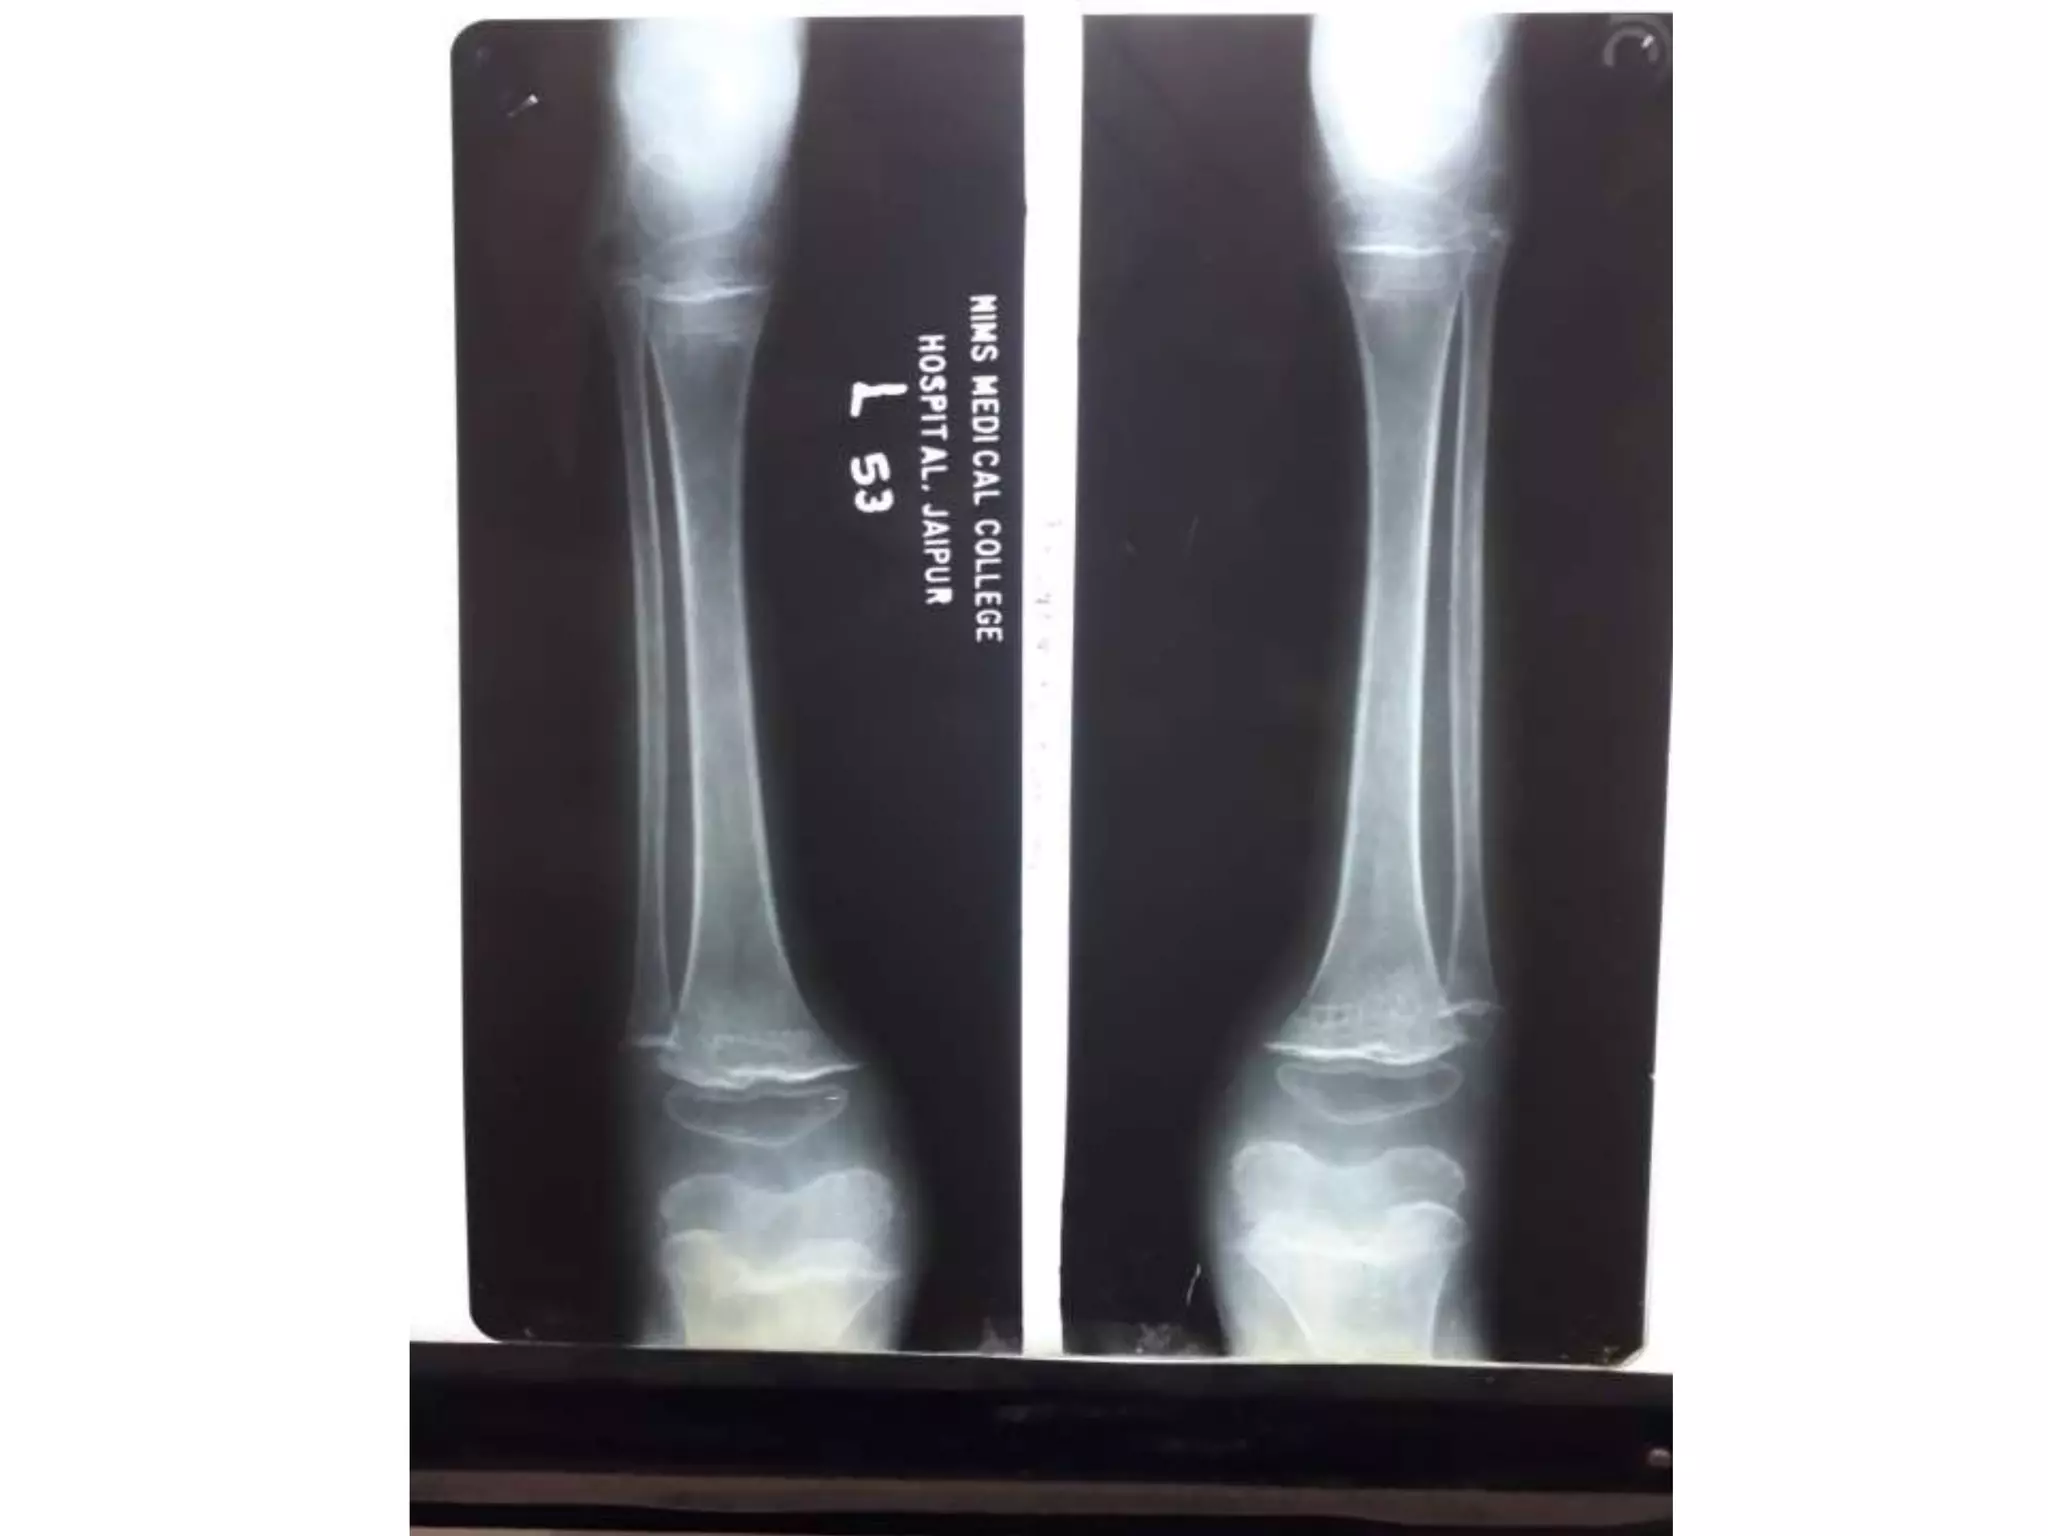

RICKETS

• Demineralization with

coarsening of the

trabecular pattern

• widening of the

epiphysis

• metaphyseal fraying,

cupping and irregularity

at the physeal margin

• Deformity (i.e. bowing)

• flared anterior ribs

RICKETS • Demineralization with coarseningof the trabecular pattern • widening of the epiphysis • metaphyseal fraying, cupping and irregularity at the physeal margin • Deformity (i.e. bowing) • flared anterior ribs